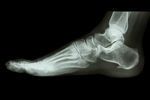

レントゲン検査などで骨の異常を確認して下さい。

骨のヒビ、骨折などの外傷が原因かもしれません。